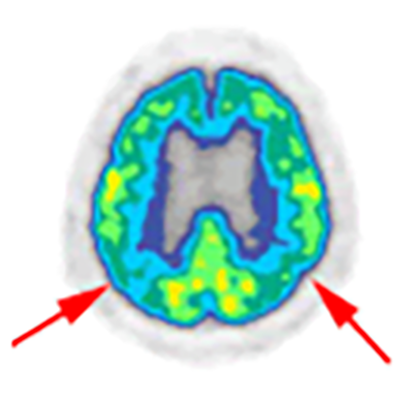

⑦認知症の診断に役立ちます

FDG-PET検査はがんの検査として注目されていますが、もとは脳の働きを調べる研究からはじまった検査方法です。

脳のエネルギー代謝や神経細胞活動の活動状態を調べることを得意とします。

特にアルツハイマー型認知症では記憶を司るところの活動が低下するためPET検査で比較的早期に発見することができます。

脳 PET(FDG)の横断図

側頭頭頂葉連合野の代謝低下が見られます。ブドウ糖の取込の度合いが記憶や理解力に関係する部位で低下するのがこの病気の特徴です。